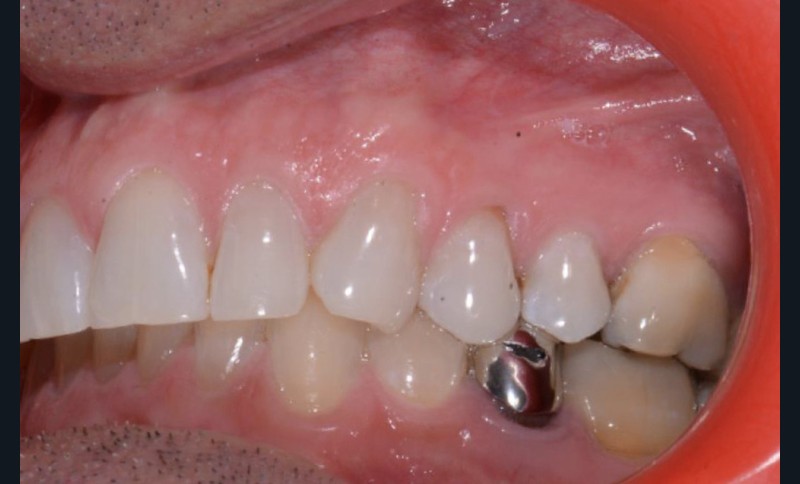

Présentation du cas clinique (fig. 1 à 3)

Le patient, âgé de 58 ans, présente un encombrement dentaire mandibulaire de 5 mm dans un contexte squelettique hypodivergent.

À la radiographie panoramique, on constate une lésion apicale sur 15 et une atteinte inter radiculaire sur 16 ainsi qu’une légère rotation de 21 sans gêne pour le patient.